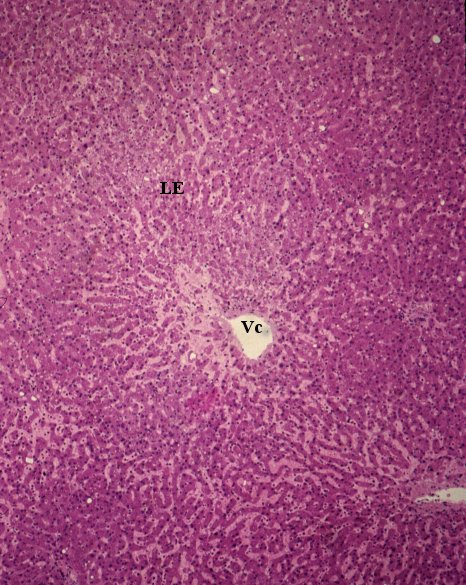

Il fegato è costituito da lobuli epatici (LE) che visti in sezione appaiono come aree poligonali separate tra di loro da strette fessure con poco connettivo: le fessure interlobulari (Fil). Nel punto di convergenza degli spigoli di più lobuli sono evidenziabili spazi più ampi detti spazi portali (Sp). Al centro dei lobuli è visibile la vena centrolobulare (Vc). (Colorazione Mallory Azan).

Visione d’insieme del parenchima epatico, è analoga alla precedente. Vi si evidenziano gli spazi portali (Sp) con all’interno il condottino bilifero, l’arteria e la vena. Le fessure interlobulari delimitano i lati di lobuli epatici (LE) adiacenti al centro dei quali si reperisce la vena centrolobulare (Vc). (Colorazione Mallory Azan).

Visione d’insieme del parenchima epatico. È analoga alle immagini precedenti. È evidente la costituzione lobulare (LE) del fegato che in sezione appare come un organo organizzato in piccole aree poligonali separate da sottili fessure che convergono agli spigoli del poligono a formare gli spazi portali. Al centro del lobulo vi è la vena centrolobulare (Vc). (Colorazione ematossilina eosina).

Il sangue pervenuto al parenchima epatico tramite le arteriole e le venule si diffonde nella rete capillare, formata da sinusoidi, per convergere al centro del lobulo epatico nella vena centrolobulare che fuoriesce dal lobulo stesso mettendo capo alla vena sottolobulare (sono le radici delle vene epatiche che sboccano poi nella vena cava inferiore). La parete della vena centrolobulare appare discontinua per la presenza dello sbocco dei sinusoidi (s). Attorno ad essa è ben evidente la disposizione a raggiera degli epatociti (ep) in cui sono riconoscibili i nuclei. (Colorazione Mallory Azan).